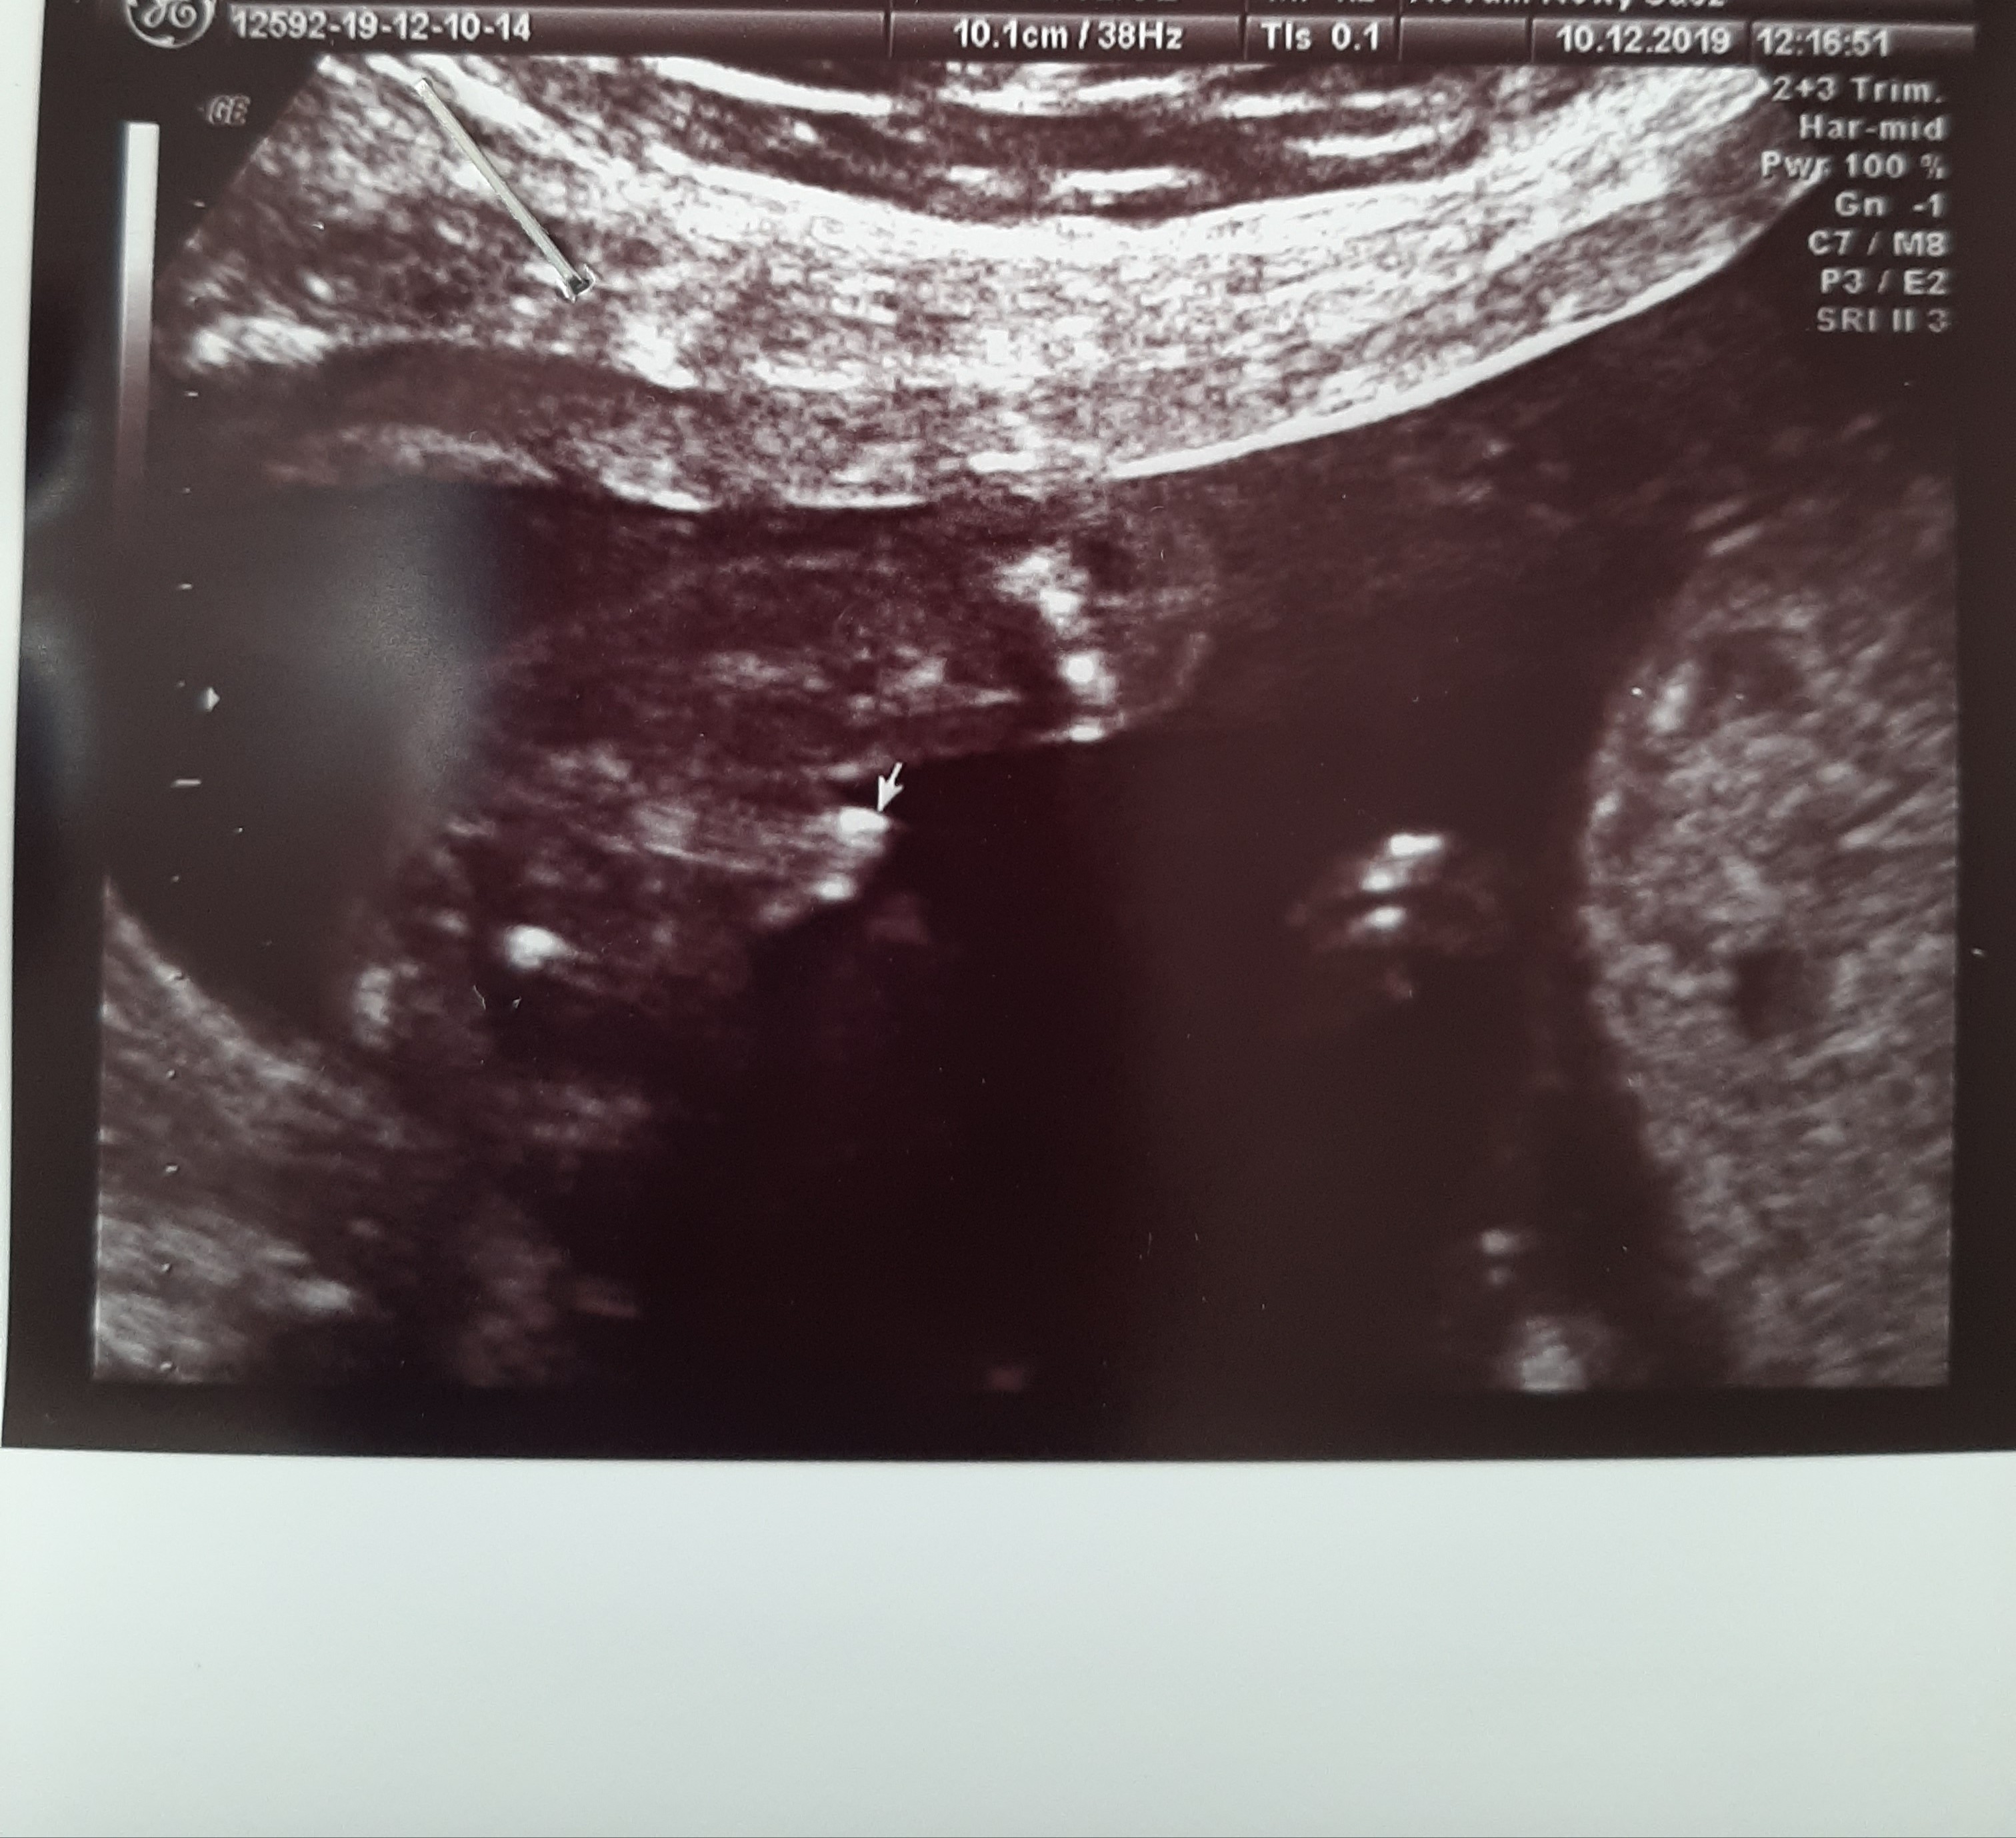

Usg chłopak czy dziewczynka

Witam w 19 tygodniu ciąży dowiedziałam się ze będę miała dziewczynkę w 20 tyg okazało się jednak , że to chłopak. Sama już nie wiem bo na jednym usg widać na pewno dziewuche a na drugim chłopca. Może to pempowina ?? Może ktoś mi pomoże rozwiązać ta zagadkę

Nie wiem kto to może być, dziwnie to wyglada. Na prącie raczej za długie, może to kawałek rączki lub pępowina 🤷🏻‍♀️

Który to tc? No i co tam lekarz mówił zaznaczając miejsce strzałką :)

Dziękuję za odpowiedź, badanie było w 18 tyg i to genetyczne a lekarz wcale jakoś mi nie zbliżył co tam jest miedzy nóżkami...powiedział że chyba chłopiec ale ja tam siusiaka nie widziałam ani jajeczek po zbliżeniu bardziej wygląda mi to na 3 kreseczki.. mój lekarz prowadzący gdzie chodzę prywatnie owszem robi mi usg na Każdej wizycie ale nie sprawdza co ma miedzy nogami.. trudno będę musiała wytrzymać do 28 żeby zrobić jeszcze 3d w ostatnim trymestrze na potwierdzenie